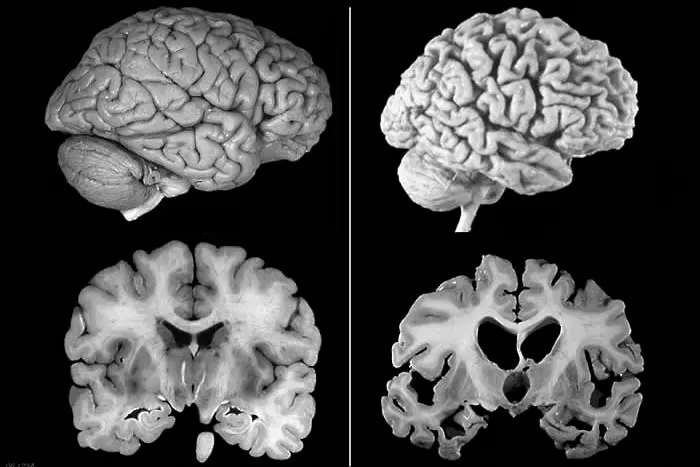

Все още няма ясна идея какво точно причинява болестта, но е ясно, че щетите върху мозъка са предизвикани от т.нар амилоидни плаки, съставени от грешно сгънати протеини. Те се разполагат около коровите клетки, сплетенията, които са разположени в мозъчните клетки или в невроните. Това води до загуба на връзките между клетките и до загуба на неврони. Заболяването се развива бавно, но упорито, и с времето мозъкът се влошава сериозно - боледуващите губят не само спомените си, но забравят как да се хранят, как да се движат, как да преглъщат, как да дишат. Повечето живеят между 8 и 12 години след диагнозата.

Новият медикамент изчиства амилоидните плаки почти напълно при високите дози след година приемане. При групите с плацебо няма разлика, а тези с по-малки дози са получили съответно по-малко изчистване.